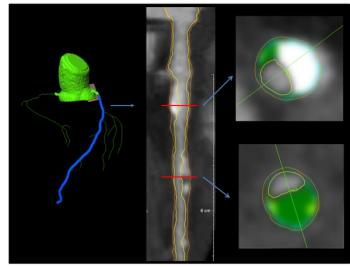

74-year-old with history of aortic valve repair at an outside hospital.